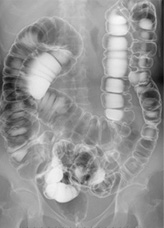

ÂÎÆâ¤ÎÍͻҤò¥ê¥¢¥ë¥¿¥¤¥à¤Ç¸«¤Ê¤¬¤é¹Ô¤¦¸¡ºº¡¦¼£ÎŤǤ¹¡£Â¤±ÆºÞ¤ò»È¤Ã¤¿°ß¤Î¸¡ºº¡¢¿©¤Ùʪ¤Î°û¤ß¹þ¤ß¶ñ¹ç¤ò¸«¤ëÓ벼¤±Æ¡¢»ÒµÜ¤Î·Á¤äÍñ´É¤ÎÄ̲á¾õÂÖ¡¢Íñ´É¼þ°Ï¤ä¹üÈׯâ¤ÎÌþÃå¤Î¾õÂÖ¤òɾ²Á¤¹¤ë»ÒµÜÍñ´É¤±Æ¤Ê¤É¡¢ÍÍ¡¹¤ÊÀìÌçŪ¸¡ºº¤ËÂбþ¤·¤Æ¤¤¤Þ¤¹¡£ºÇ¿·¤ÎÄãÈï¤Ð¤¯ÁõÃÖ¤òƳÆþ¤·¤Æ¤ª¤ê¡¢°ÂÁ´Ì̤ˤâÇÛθ¤·¤Æ¤¤¤Þ¤¹¡£